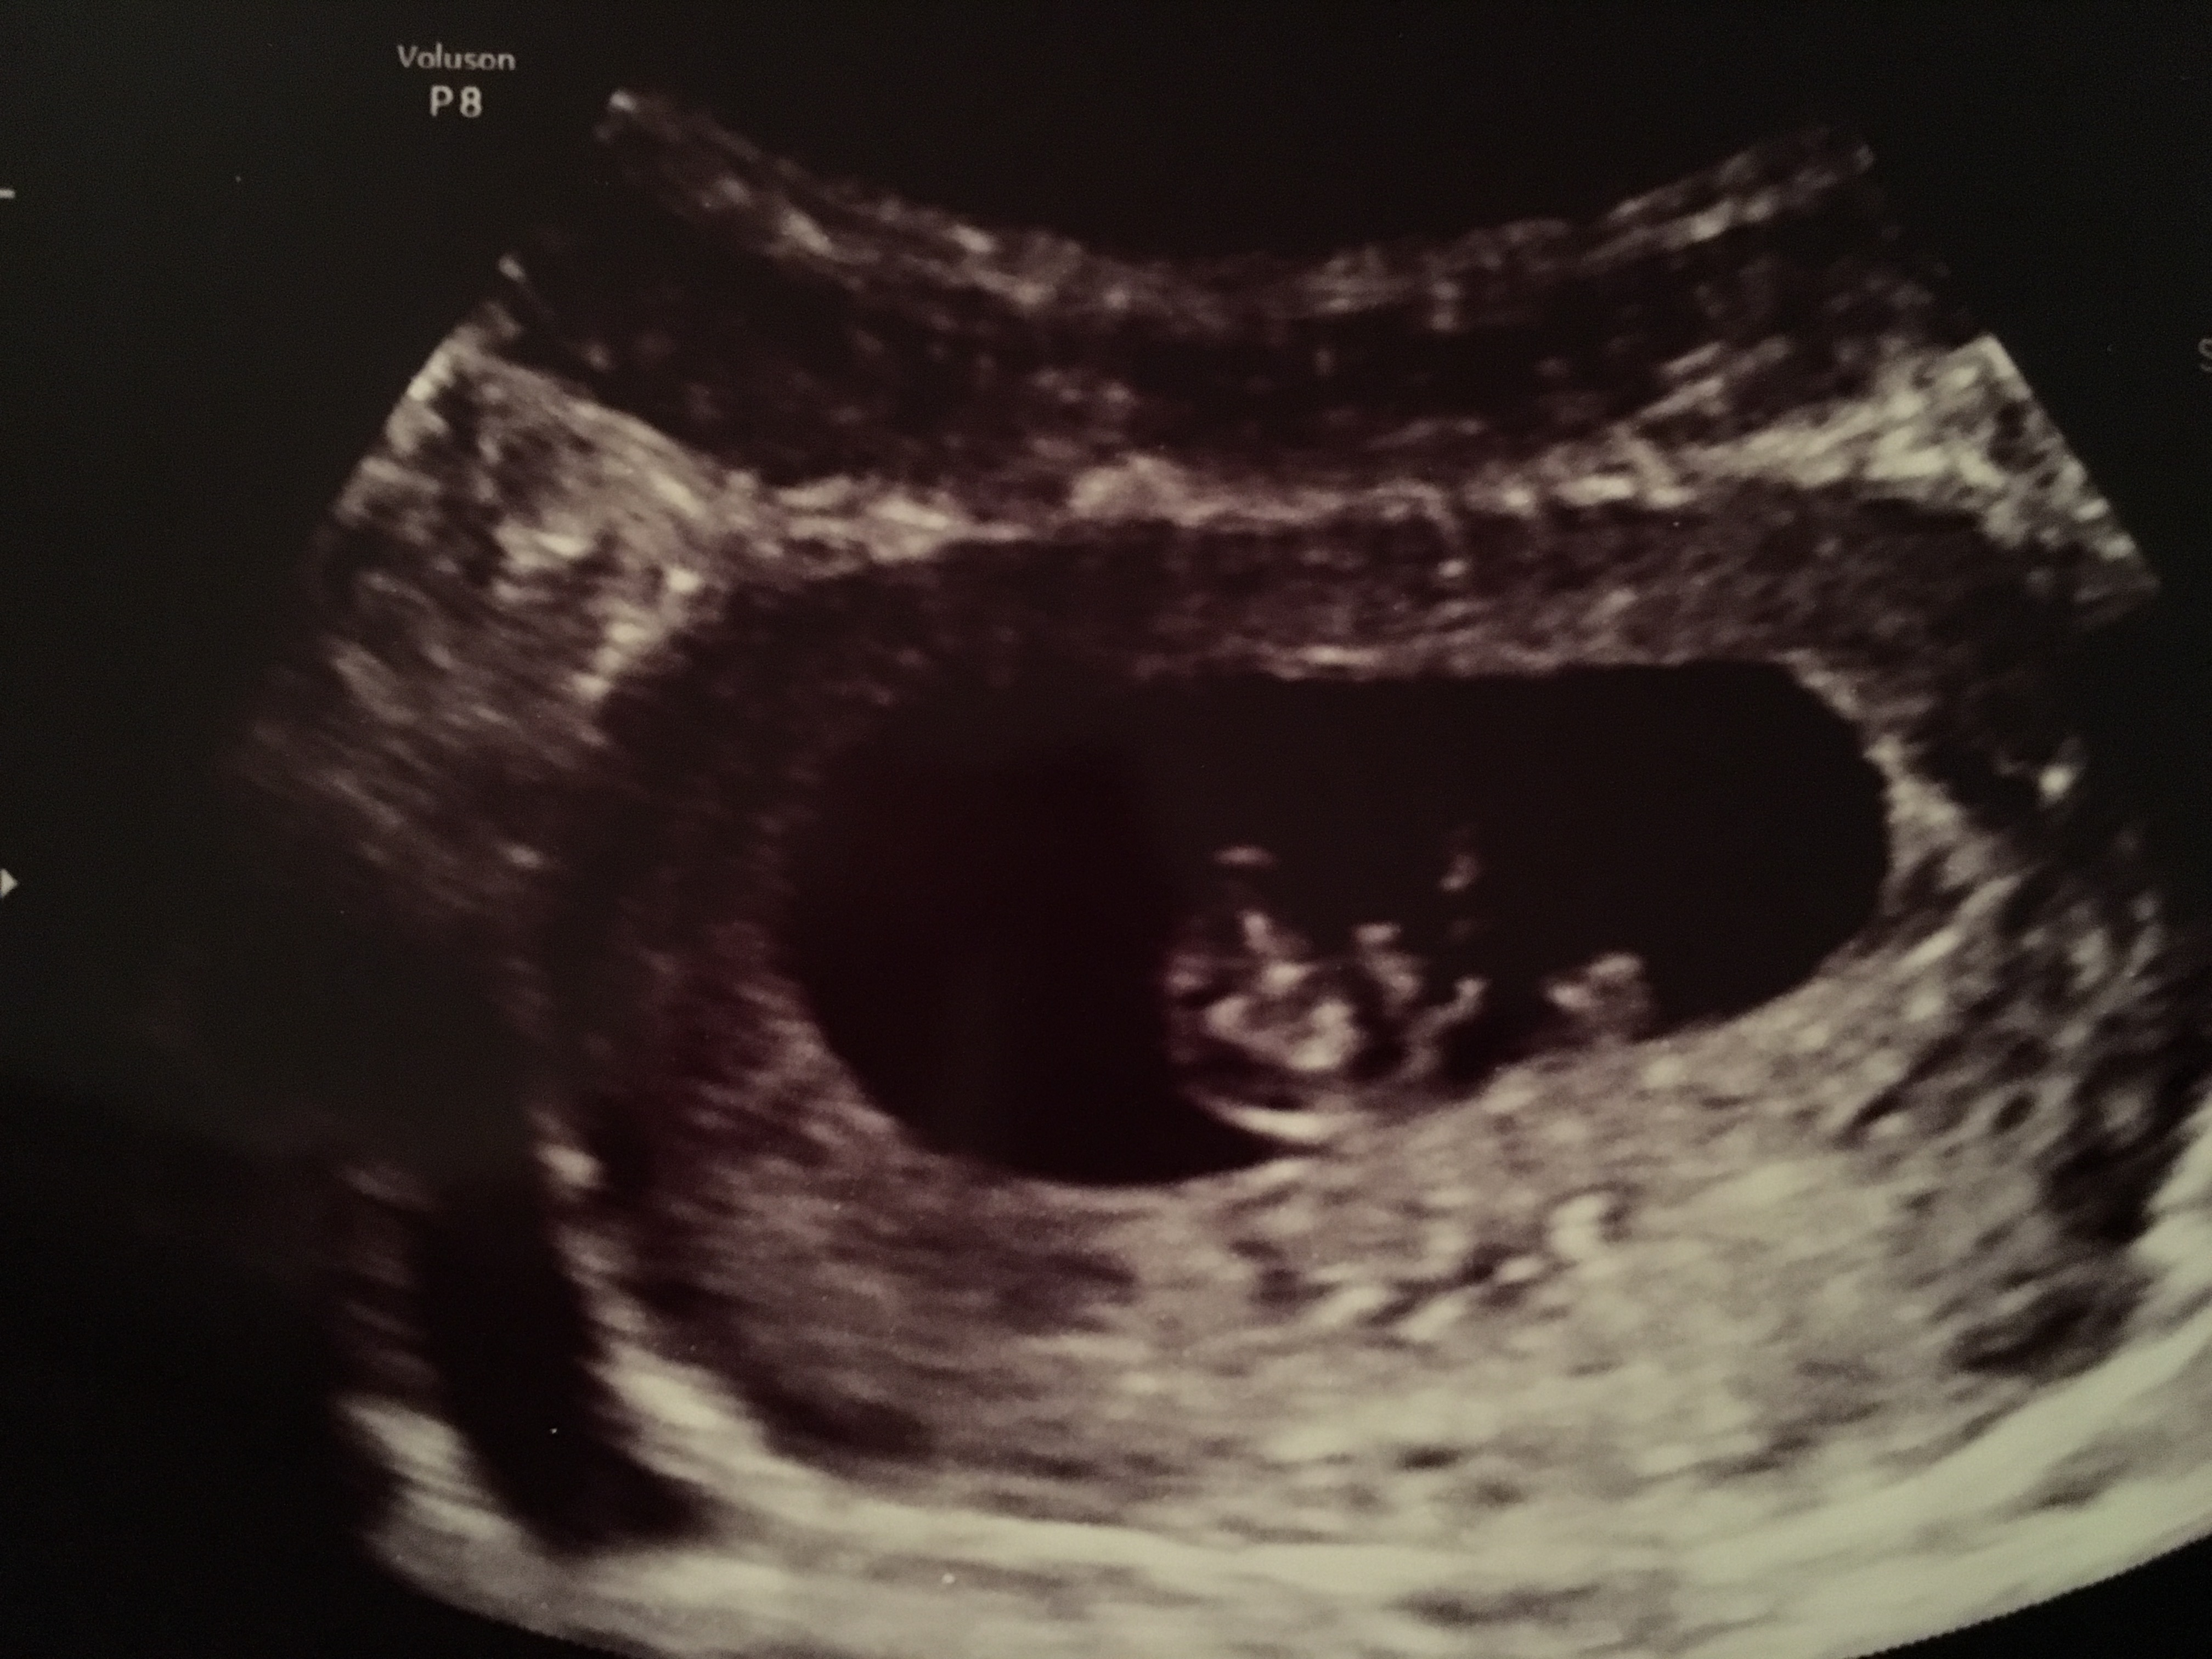

We had our first ultrasound on wednesday November 4th and to our suprise! It's twins! The tech turned to us almost immediately and said ummm there is two in there lol. Both babies 7wks 1day. Baby A heartbeat 158, Baby B hb 151